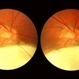

- Color fundus photograph of the right eye of a 61-year-old Caucasian female shows that as disease progresses, parafoveal capillaries become dilated temporally and then circumferentially around the fovea. The vessels also appear to make “right angle” turns as they plunge into deep retina. Punctate crystals may form at the vitreoretinal interface in almost half of MacTel type 2 patients and do not correlate with disease progression. This patient had bilateral asymmetric disease involvement, which is typical for MacTel type 2.